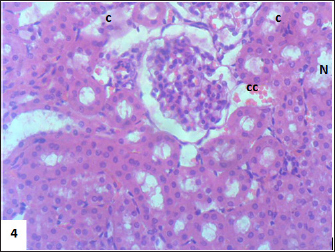

Mouse liver from the control group shows a normal radiant arrangement of the hepatic cells (Fig. 1). Pathological changes in treated liver sections showed an increase in the immune cells’ infiltration, and marked congestion were observed in almost all mice. In group 1, there was hemorrhage, congestion, and degenerated cells (Fig. 2). In group 2, there was congestion of the central vein, infiltration of immune cells, and degeneration of hepatocytes (Fig. 3). Whereas in group 3, the previously mentioned changes were markedly intensified with severe hemorrhage and marked sinusoidal dilatation (Fig. 4). Mouse kidney of control group shows normal cellular appearance (Fig. 5); however, pathological changes in treated kidneys sections reveals congestion, tubular necrosis and cast in some tubule’s lumen, group 1 (Fig. 6). In group 2, there was congestion, tubular necrosis, necrotic debrites in the tubuli lumen and cast (Fig. 7). Whereas in group 3 there was marked congestion, tubular and cellular necrosis, necrotic debrites in the tubular lumen and degenerated cells (Fig. 8).

Fig. 5. Section of mouse kidney of control group shows normal cellular appearance (H and E, ×400).

Fig. 6. Section of mouse kidney fed with 1 mg/kg Lorazepam showing congestion (cc), tubular necrosis (N), and cast (c), (H and E, ×400).